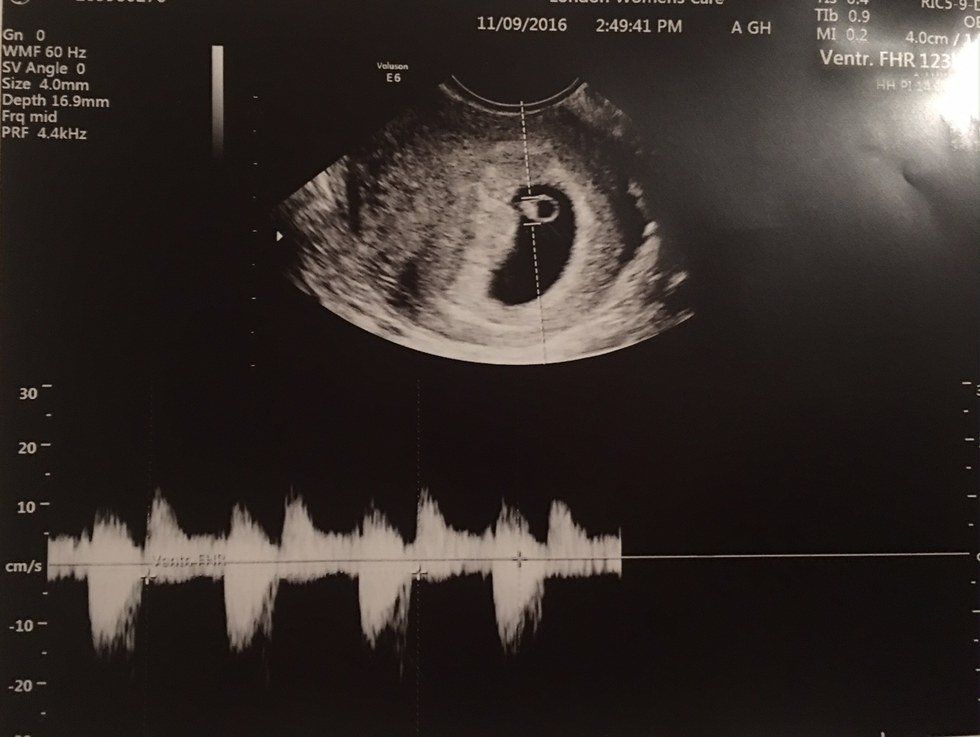

A rainbow baby is a baby that is conceived after a miscarriage. Today, November 12, 2016, I am 6 weeks and 3 days pregnant with my rainbow baby.

Thursday, October 27, for a reason still completely unknown to us I received information in the mail from my insurance company congratulating me on my pregnancy. Remember, at this point, I'm not pregnant and still hadn't even told my health insurance about the pregnancy I had lost. At 2:15 p.m. that same day we went for my post-miscarriage doctor appointment and on that day (exactly a month right down to the day from miscarrying the first baby) I tested positive at two weeks gestation by means of a blood test.